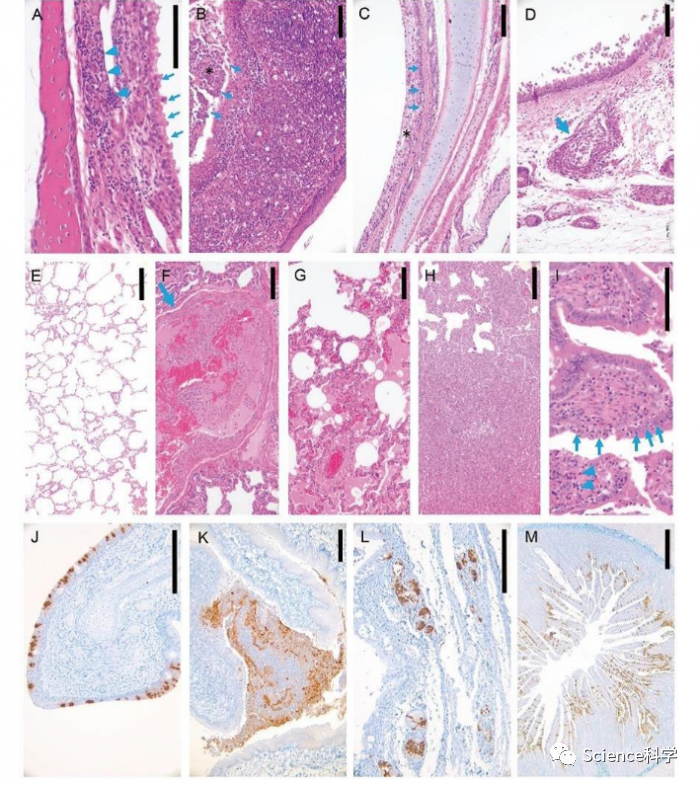

美国《科学》杂志8日发表的新研究发现,新冠病毒容易感染猫和雪貂,而对狗、猪、鸡、鸭等感染性微弱。目前,对于新冠病毒起源以及中间宿主等还没有定论,哪种动物最适合作为实验模型来评估新冠药物和疫苗对人体的功效仍是一大难题。在这一研究中,研究人员比较研究了不同动物对新冠病毒的敏感性,包括猫、狗、猪、鸡、鸭等家畜。

研究选取了两个病毒株:F13-E和CTan-H。研究人员通过动物的鼻腔接种使其感染新冠病毒,然后检测病毒在各部位的复制情况。结果发现,病毒在其他动物体内复制很少,但在雪貂上呼吸道、猫的呼吸系统和消化系统复制较多。幼猫的感染更为严重。

研究负责人、中国农业科学院哈尔滨兽医研究所研究员、中国科学院院士陈化兰在接受新华社记者书面采访时表示,这项研究证明,雪貂可以用作新冠病毒疫苗和药物评估的模型动物。猫高度易感,应该密切监测和保护疫区的猫。狗、猪和家禽等动物对新冠病毒不易感。该研究将对新冠病毒的溯源具有重要指导意义。